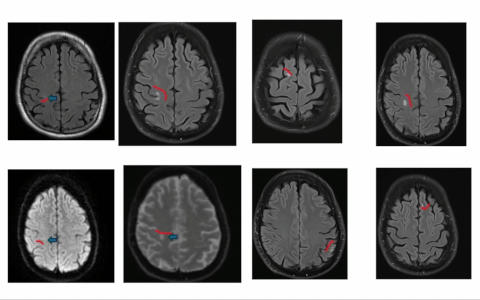

Neurologia